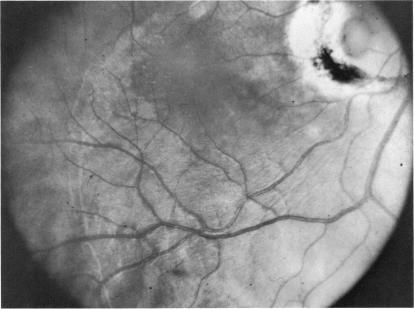

Six cases of congenital pit of the optic nervehead associated with posterior serous retinal detachment are presented. All were treated by photocoagulation along the disc margin in the area of retinal detachment. In five cases reattachment of the retina occurred, after the clinical development of a film chorioretinal adhesion at the disc margin, and appeared to be secondary to the treatment. The sixth case (Case 4), although treated, appeared to represent a spontaneous reattachment. This disorder, which frequently results in permanent decrease of central vision, affected the better, or only, eye in two of the six cases herein reported. Fluid, probably from the vitreous cavity, appears to gain access to the subretinal space via the pit. Reattachment in treated cases occurred only if an effective chorioretinal adhesion was created over the entire area of the fistulous detachment at the disc margin. Field defects after treatment appear to be secondary to either the optic pit itself or the longstanding retinal detachment, oftern accompanied by pigmentary degeneration and cystic macular degeneration, rather than juxtapapillary photocoagulation treatment.

本文报告6例先天性视神经乳头凹合并浆液性视网膜脱离。所有病例均采用视网膜脱离区域沿视盘边缘光凝治疗。5例视网膜脱离在视盘边缘形成脉络膜视网膜粘连后复位,似乎是治疗的继发结果。第6例(病例4)虽经治疗,但似乎是自发复位。这种疾病常导致中心视力永久性下降,在本文报告的6例中有2例影响了较好或仅有的一只眼。液体可能来自玻璃体腔,似乎通过视神经乳头凹进入视网膜下间隙。治疗病例中,只有在视盘边缘瘘管性脱离的整个区域形成有效的脉络膜视网膜粘连时,视网膜才会复位。治疗后的视野缺损似乎继发于视神经乳头凹本身或长期视网膜脱离,常伴有色素性变性和黄斑囊样变性,而非视盘旁光凝治疗。